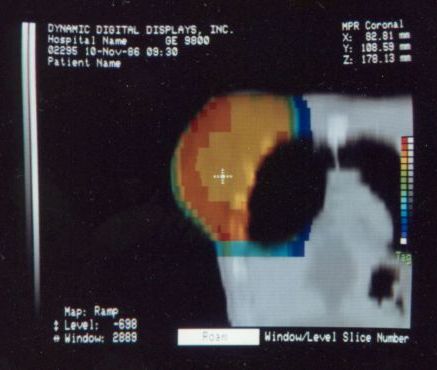

These photos of the Voxelscope II screen are typical of the types of rendering provided by the system.

Voxelscope II Screen Shots. Combination of 3-D Shaded Surface, Multiplanar Reformatting, and Segmentation

Of course, once there was a real Marketing department, the real Software types (led by Eddie Wyatt) were always slowing things down anyhow in the interest of generality - or to concentrate on features users might actually care about! What a conecpt? ;-) One example was Multi-Planar Reformatting or MPR where a single cut along one of the principal planes - axial (XY), saggital (YZ), coronal (XZ) - or at an arbitrary angle or even curved cut through the object is displayed. MPR could have run at full video rates on any of the machines, but no matter how hard I tried to convince Software to improve the performance, it never chugged along at more than a couple frames per second. :( :) And large portion of the VS2 hardware capabilities were never exploited due to feature priority as determined by Marketing.